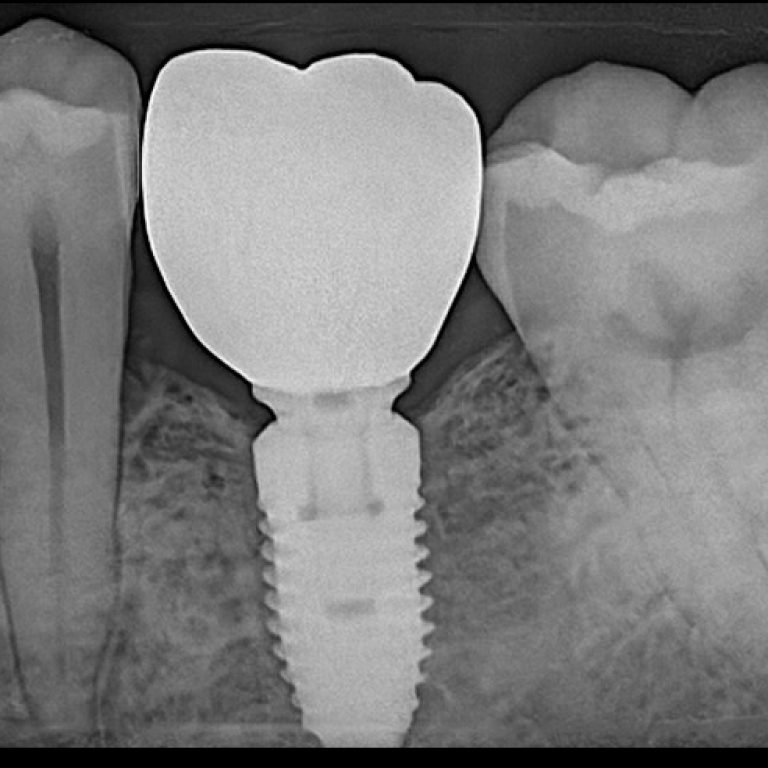

Best Dental Implant Clinic in Dhaka at Banani Take Another Chance to Smile and Visit best dental implant clinic in Dhaka Looking for best dental implant … by rahman.smm@gmail.comJanuary 5, 2026